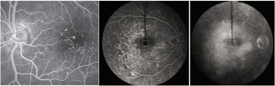

Fluorescein angiography (Figure 1) and optical coherence tomography (OCT; Figure 2) are 2 common tests to evaluate macular edema. Based on the appearance of fluid on these tests, macular edema may be widespread, localized, or be made up of many small blisters surrounding the center of the macula—a common form called cystoid macular edema.